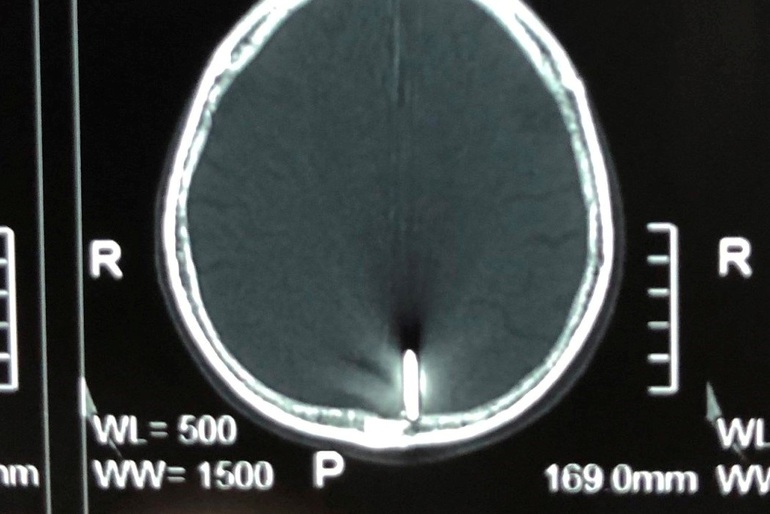

Hình ảnh cây đinh trên phim chụp cắt lớp sọ não (Ảnh: BV cung cấp).

Theo bệnh viện, cụ Đ. vào viện với tình trạng tỉnh táo, đường kính đầu dị vật khoảng 5 mm ở đỉnh đầu bên trái gần đường giữa. Kết quả chẩn đoán hình ảnh dị vật là kim loại khoảng 3-4 cm cắm vào não vùng đỉnh bên trái, cạnh xoang tĩnh mạch dọc trên.

BS CK2 Chương Chấn Phước, Trưởng khoa Ngoại thần kinh, cho biết đây là tai nạn rất ít gặp do bệnh nhân có chủ ý gây ra nhưng nguy hiểm đến tính mạng. Bệnh nhân này rất may mắn khi cây đinh không đâm trúng các cấu trúc quan trọng của não. Đặc biệt, cây đinh nằm rất gần xoang tĩnh mạch sọ, chỉ cần lệch về bên phải 5-10 mm thì tiên lượng rất nặng, khả năng phẫu thuật thất bại cao, kể cả tử vong trên bàn mổ.